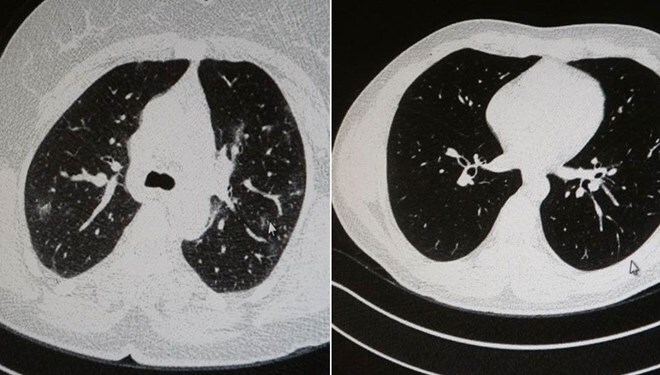

Genç olduğu halde aşı olmayanlarda hastalığın ağır seyrettiğini ifade eden Uzm. Dr. Azar, “Ben gencim, benim bağışıklık sistemim kuvvetli” diyen genç bir hastanın akciğerlerinde ciddi lekelenmelerin olduğunu ve corona virüs zatürresi olduğunu gördüklerini belitti.

Uzm. Dr. Azar, aynı şekilde aşı olup corona virüs hastalığına yakalanan bir başka genç hastanın akciğer tomografisinde akciğerde herhangi bir sorunun olmadığını ve hastanın durumunun iyi olduğunu gözlemlediklerini kaydetti. Uzm. Dr. Azar, sürekli şahit oldukları “Keşke biz aşı olsaydık” sözünü bir daha duymamak için herkesi aşı olmaya davet etti.